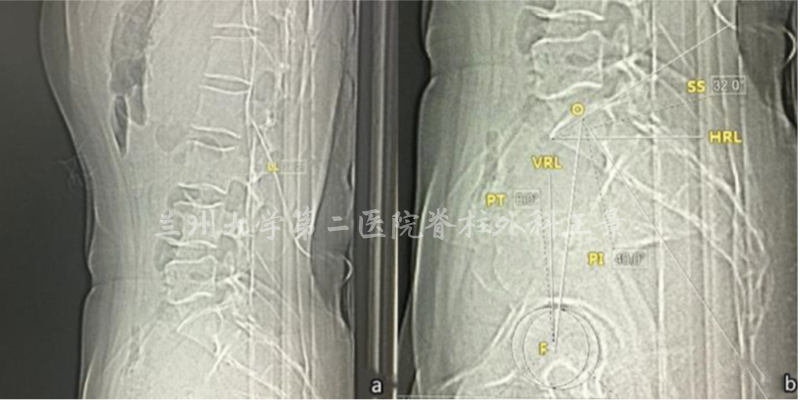

比如腰骶部矢状面平衡参数

PACS测量PT=8°,SS=32°,PI=40°

对着同一张片子

掏出iPhone,尽量正对拍摄

实际上稍微歪一点也没关系

打开照片,进入编辑模式

手指按着屏幕旋转照片

iOS自带的功能

图片旋转时会显示网格线及旋转角度

顺时针/逆时针旋转分别显示±°

精度为1°

如图所示旋转照片

S1上终板与水平线重叠/平行

旋转角度就是骶骨倾斜角

即SS=32°

再重新旋转图片

让股骨头中垂线与网格垂线重叠

旋转角度就是PT(-8°)